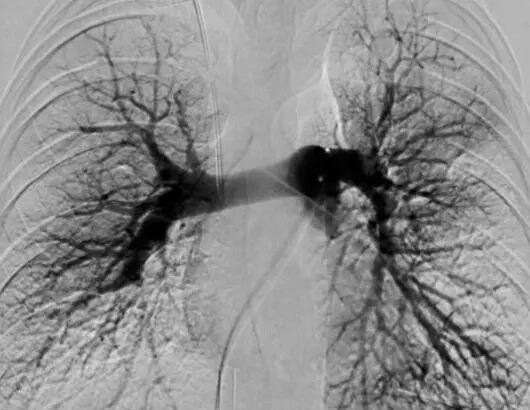

患者1-术毕造影提示绝大部分肺血栓已取出

患者2-术毕造影提示绝大部分肺血栓已取出